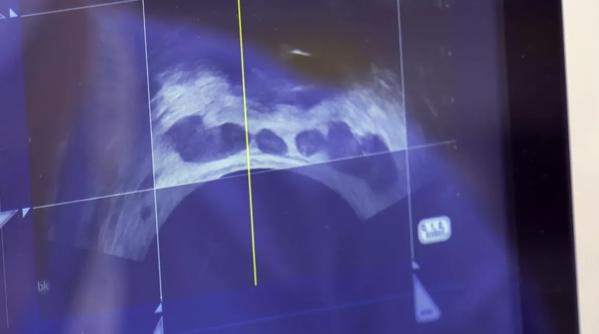

And for intermediate-level cancer, they could be eligible for high-intensity focused therapy, which uses ultrasound waves to get rid of the cancer.

This kind of procedure can help reduce common side effects like urinary incontinence and erectile dysfunction.